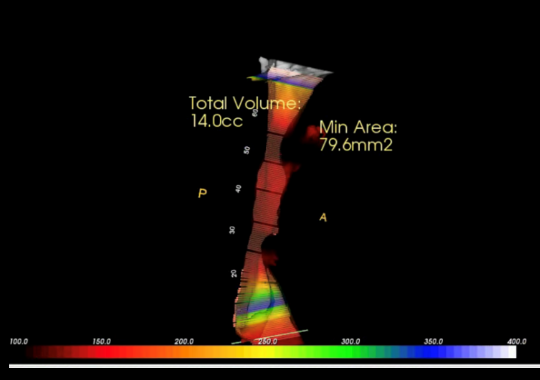

Exámen de Via Aérea Volumetría

Mediante el CBCT podemos analizar la vía aérea en toda su extensión tanto anteroposterior como lateral,

Lo que nos permite evaluar factores de riesgo para desarrollar OSA y predictibilidad de algunos tratamientos